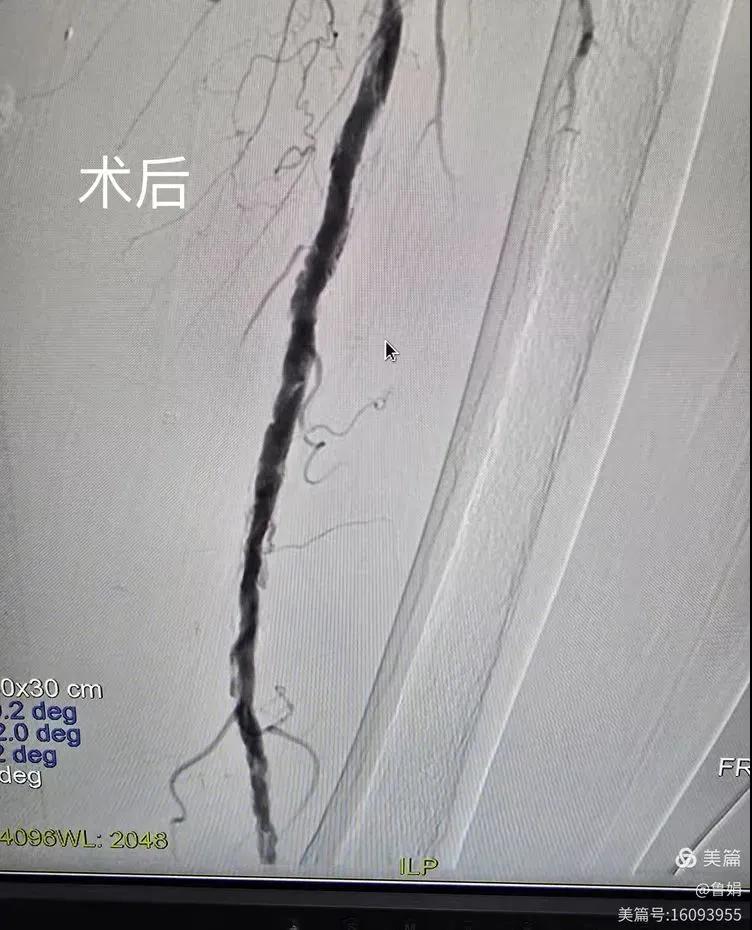

據(jù)悉,該患者,女,73歲,下肢動(dòng)脈硬化閉塞癥,“以靜息痛,間歇性跛行”入院,CTA評(píng)估:股淺動(dòng)脈,腘動(dòng)脈間斷性多段重度狹窄,外二科血管外科團(tuán)隊(duì)根據(jù)患者病情,結(jié)合檢查結(jié)果,經(jīng)過科室會(huì)診后,決定對(duì)該病人行介入治療。手術(shù)由周創(chuàng)業(yè)副主任與北大一院血管外科專家郭宏杰教授聯(lián)合開展,對(duì)股淺動(dòng)脈,腘動(dòng)脈重度閉塞段行血管開通+藥涂球囊擴(kuò)張成形,術(shù)后狹窄明顯緩解,血流恢復(fù)!